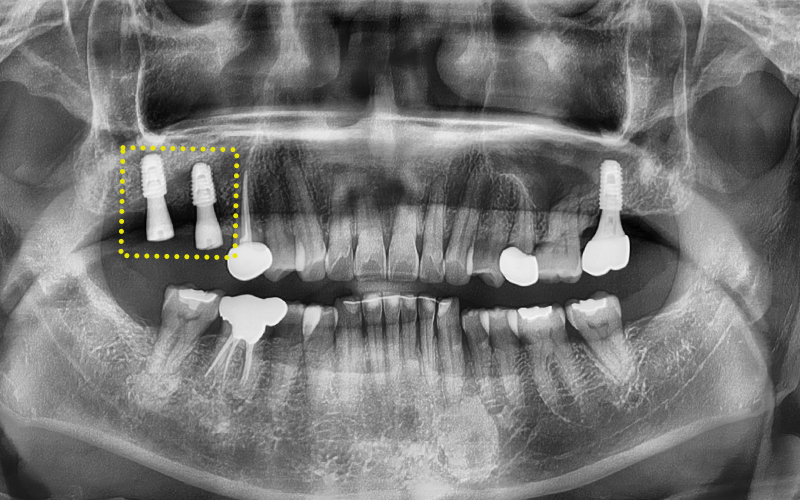

✅ Problems seen on X-ray

We then took X-ray and CT images

to precisely check the condition inside the mouth.

After looking at the X-ray, the patient also said,

"Even I can see it seems to be placed too far back."

After confirmation, maxillary sinus lift surgery

had been attempted twice but failed,

and in the end, the implant had been placed in a position

far back, similar to the location of a wisdom tooth.

Although the implant itself had successfully osseointegrated,

because the position was unclear,

it was a very unfavorable situation for fabricating the prosthetic restoration...!

In addition, the tooth in the front that was undergoing root canal treatment

had a poor prognosis and needed extraction.